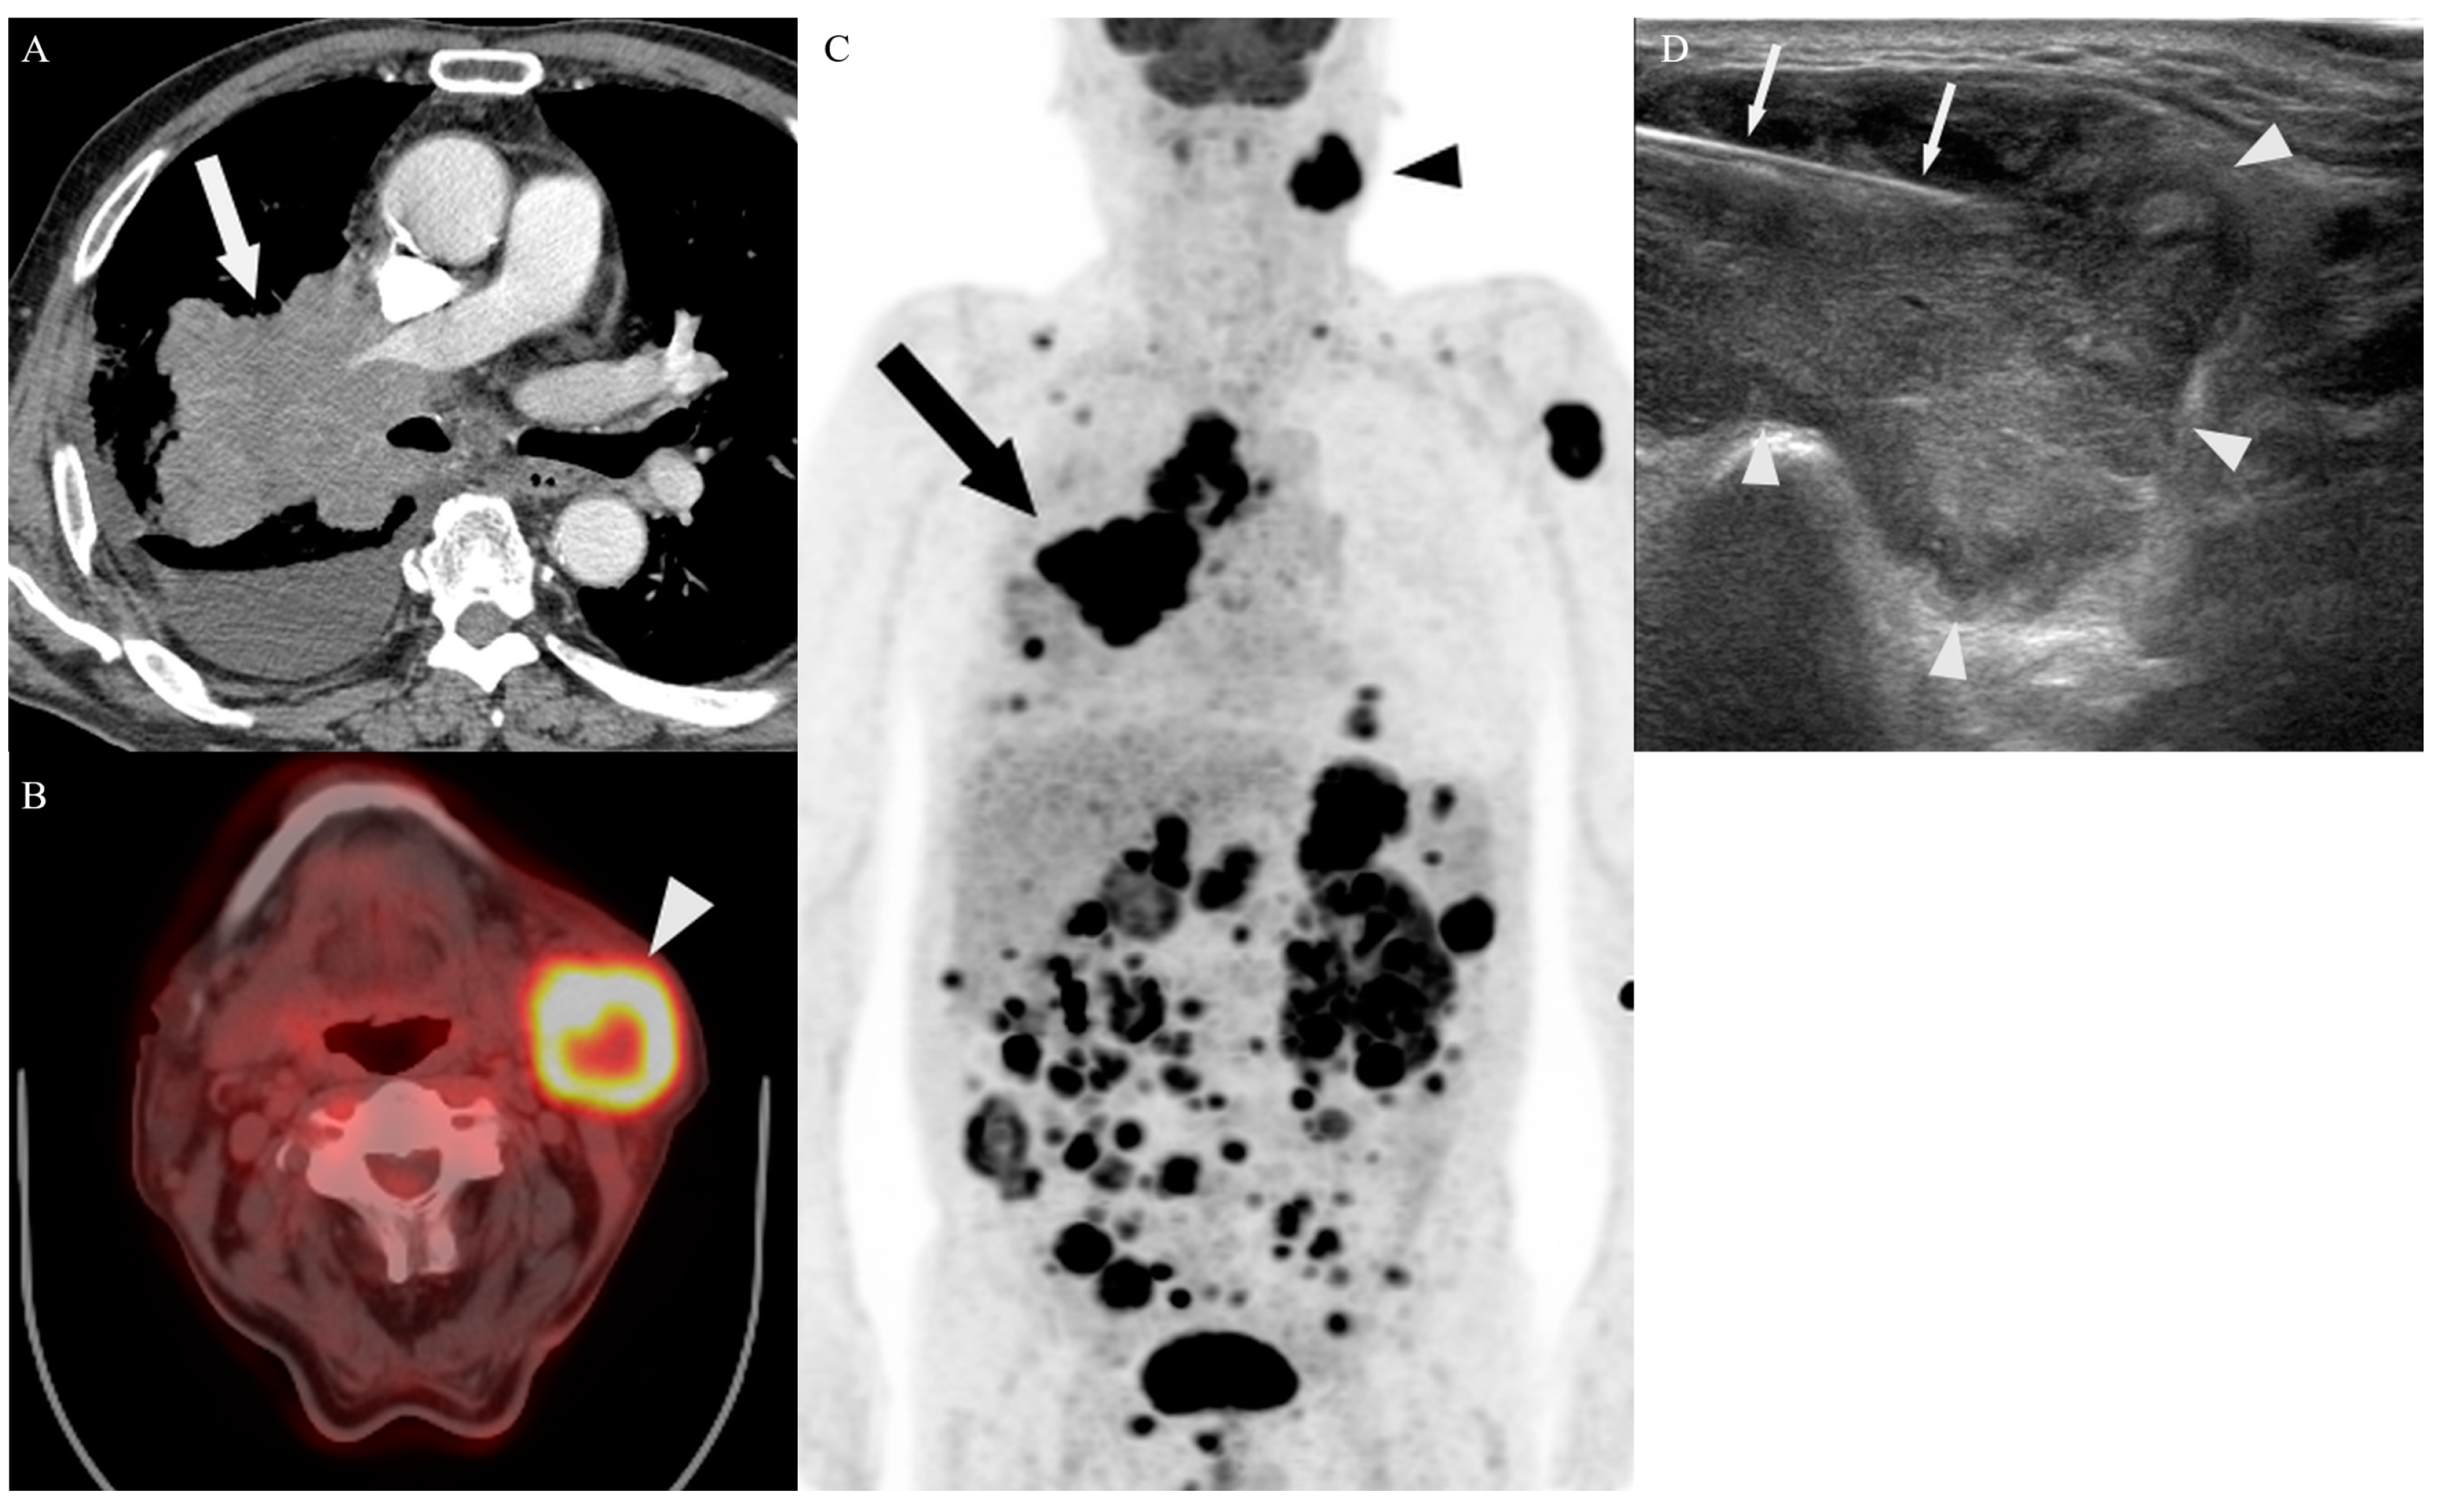

3.2. Biopsy Characteristics and Outcomes

3.4. Target Site Selection, Complications, and Diagnostic Yield According to PET/CT Timing